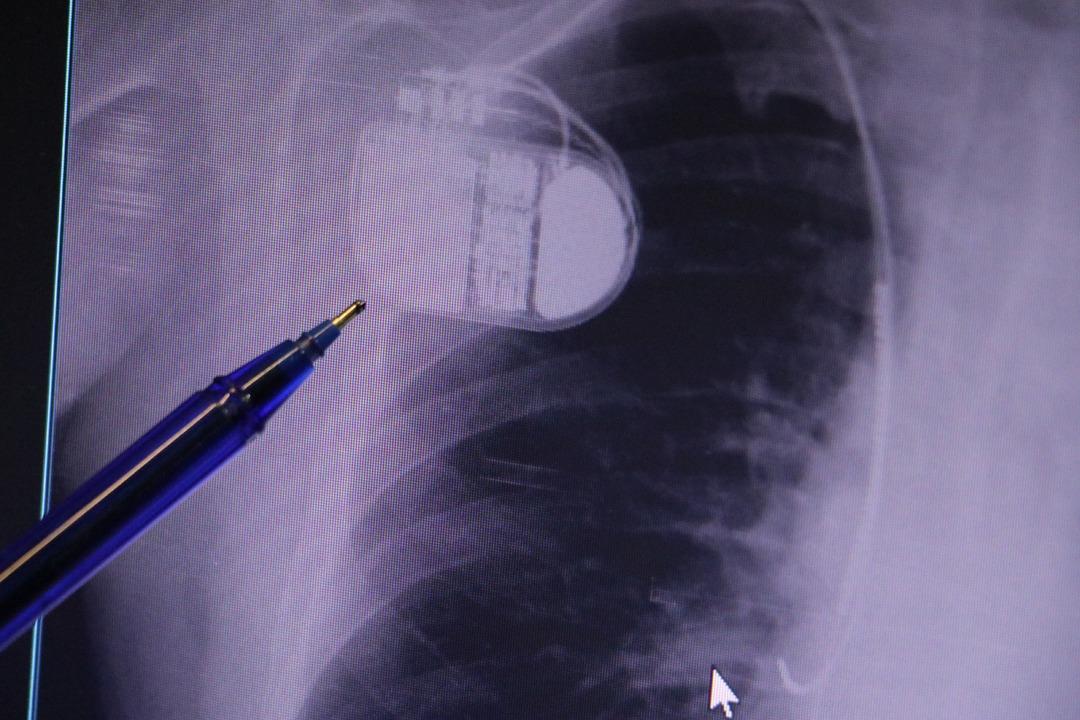

Kalp krizi sonrası kalp dokusunun zarar gördüğünü belirten İsmail Erdoğu, şöyle konuştu: “Kalp hastalığı günümüzde dünyada en sık görülen ölüm nedenlerinden biridir. Kalp hastalıklarının pek çok grubu vardır. Kalp hastalığı dediğimizde sadece kalpte stent bulunan ve damar sorunları olan kişileri kastetmiyoruz. Aynı zamanda hipertansiyon ve şeker hastalığı olan hastalar da kalp hastalığına adaydır. Toplumun yaklaşık %30-35’ini kapsıyoruz. Oldukça yaygın bir hastalıktır ve bu konuda teknolojik ve tıbbi anlamda ciddi gelişmeler yaşanmıştır. Son 30 yılda insanlar kalp rahatsızlığı nedeniyle hastaneye kaldırıldı.” “Hastaneye yattıktan sonra hayatta kalmak artık mümkün. Kalp krizinden kurtulmanın belli bir maliyeti var. Kalp krizinden sonra kalp yetmezliği ortaya çıkıyor. Kalp yetmezliği olan hastalarda aritmiler, ani ölümler gibi sorunlar ortaya çıkabiliyor. Hastaların bu uzun vadeli rahatsızlıklardan kendilerini korumak için mutlaka kalp piline ihtiyaçları var” dedi.

MR makinesine kalp pili takılmasının mümkün olduğunu belirten Erdoğu, şöyle konuştu: “Çok büyük bir ameliyat değil ama yine de ciddi bir cerrahi işlem. Kalp pili tıpta son 30 yılın en büyük gelişmesi. Aslında bilgisayarın minyatürleştirilmiş hali olup insan vücuduna yerleştirilen bir tedavi. İnsan ömrünü önemli ölçüde uzatan bir tedavi. İnsanlar şokla hayata tutunurken, pil olmasaydı öleceğini düşündüğümüz çok sayıda hastamız var. Bu özelliğimiz Kalp pili uygun hastalarda ani ölümü önler, ritmi düzeltecek sağlık uzmanı ya da defibrilatör yoksa hastayı hayatta tutmak mümkün değildir. Hastalarımız “kalp pilim var” dediğinde hastalıktan kurtulurlar. Örneğin mikser kullanmak ya da kolu sallayacak herhangi bir hareket kalp pilini olumsuz etkileyebilir. Soğuk havalarda vücutta meydana gelen şiddetli titremeler kalp pilinin hafızasını karıştırıp gereksiz şoklara neden olabilir.